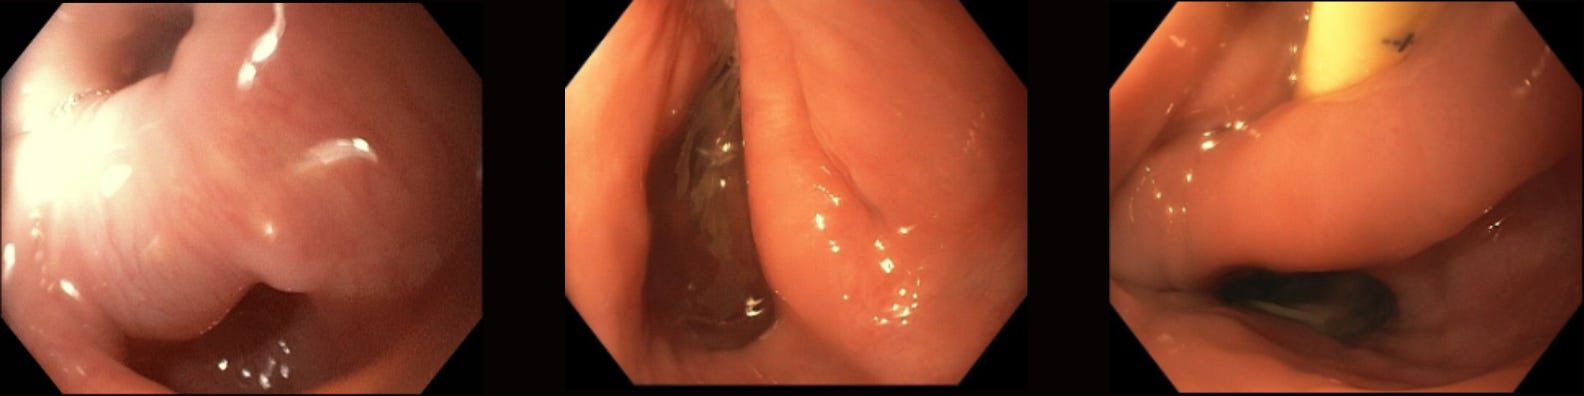

The use of a distal transparent endoscopic cap may assist during the incision/resection process.

In this case of Zenker's diverticulum we can see how the cap:

(a) stabilizes the view

(b) allows for focused attention of the target

(c) maintains a safe distance between the scope tip and the diverticular septum. All of these aspects permits a directed and controlled incision. Additionally, the cap allows for blunt dissection and the ability to achieve hemostasis via tamponade if any bleeding were to occur.